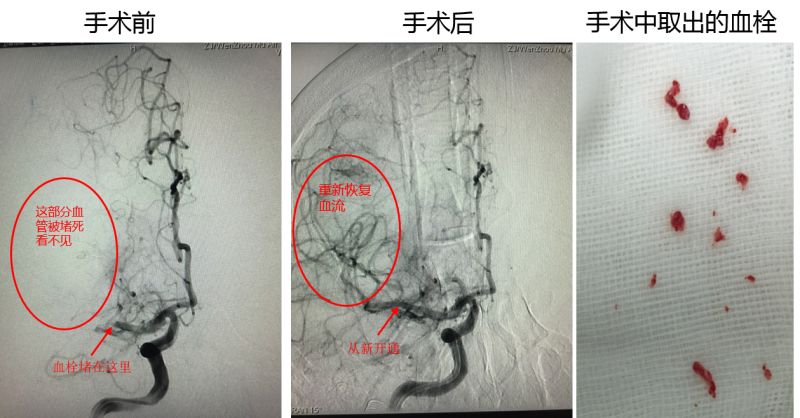

首先,在全身麻醉的数字减影血管造影(DSA)设备辅助下,医生在王女士的大腿根部股动脉内穿针,将一个阀门安装在股动脉内。阀门的一端在体外,一端则在股动脉内,于是形成了一个通路。紧接着,医生用直径为2毫米的导管穿过股动脉,到达大脑中动脉,将一个取血栓的金属支架通过导管塞了进去,在影像设备的照射下,医生将网状的金属支架塞入到达血栓位置。

接下来,医生适当拉出一点金属网,使其完全张开。网张开后,就将血栓网住了。这样一来,医生再将导管连同金属网一起拉出,血栓就被拉出体外了。血栓通过2次才拉出来,好比用渔网网鱼,不过血栓不像鱼,血栓是固定的。据悉,术后患者病情稳定、意识逐步清醒,24小时内就转出了ICU。经过一周的康复治疗,目前王女士已经痊愈出院。